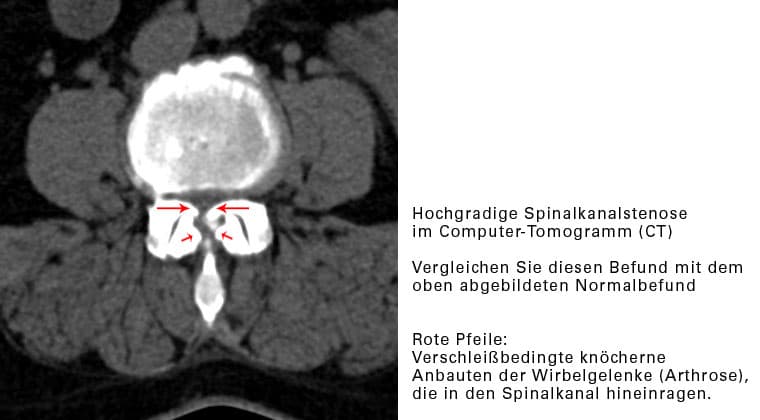

Es liegt eine krankhafte Verengung des Wirbelkanales vor (Stenose des Spinalkanales). Diese tritt in der Regel erst in höherem Alter auf. Sie wird verursacht durch:

• Verschleiß von Wirbeln und Wirbelgelenken, die knöcherne Anbauten entwickeln, welche in den Wirbelkanal hineinragen